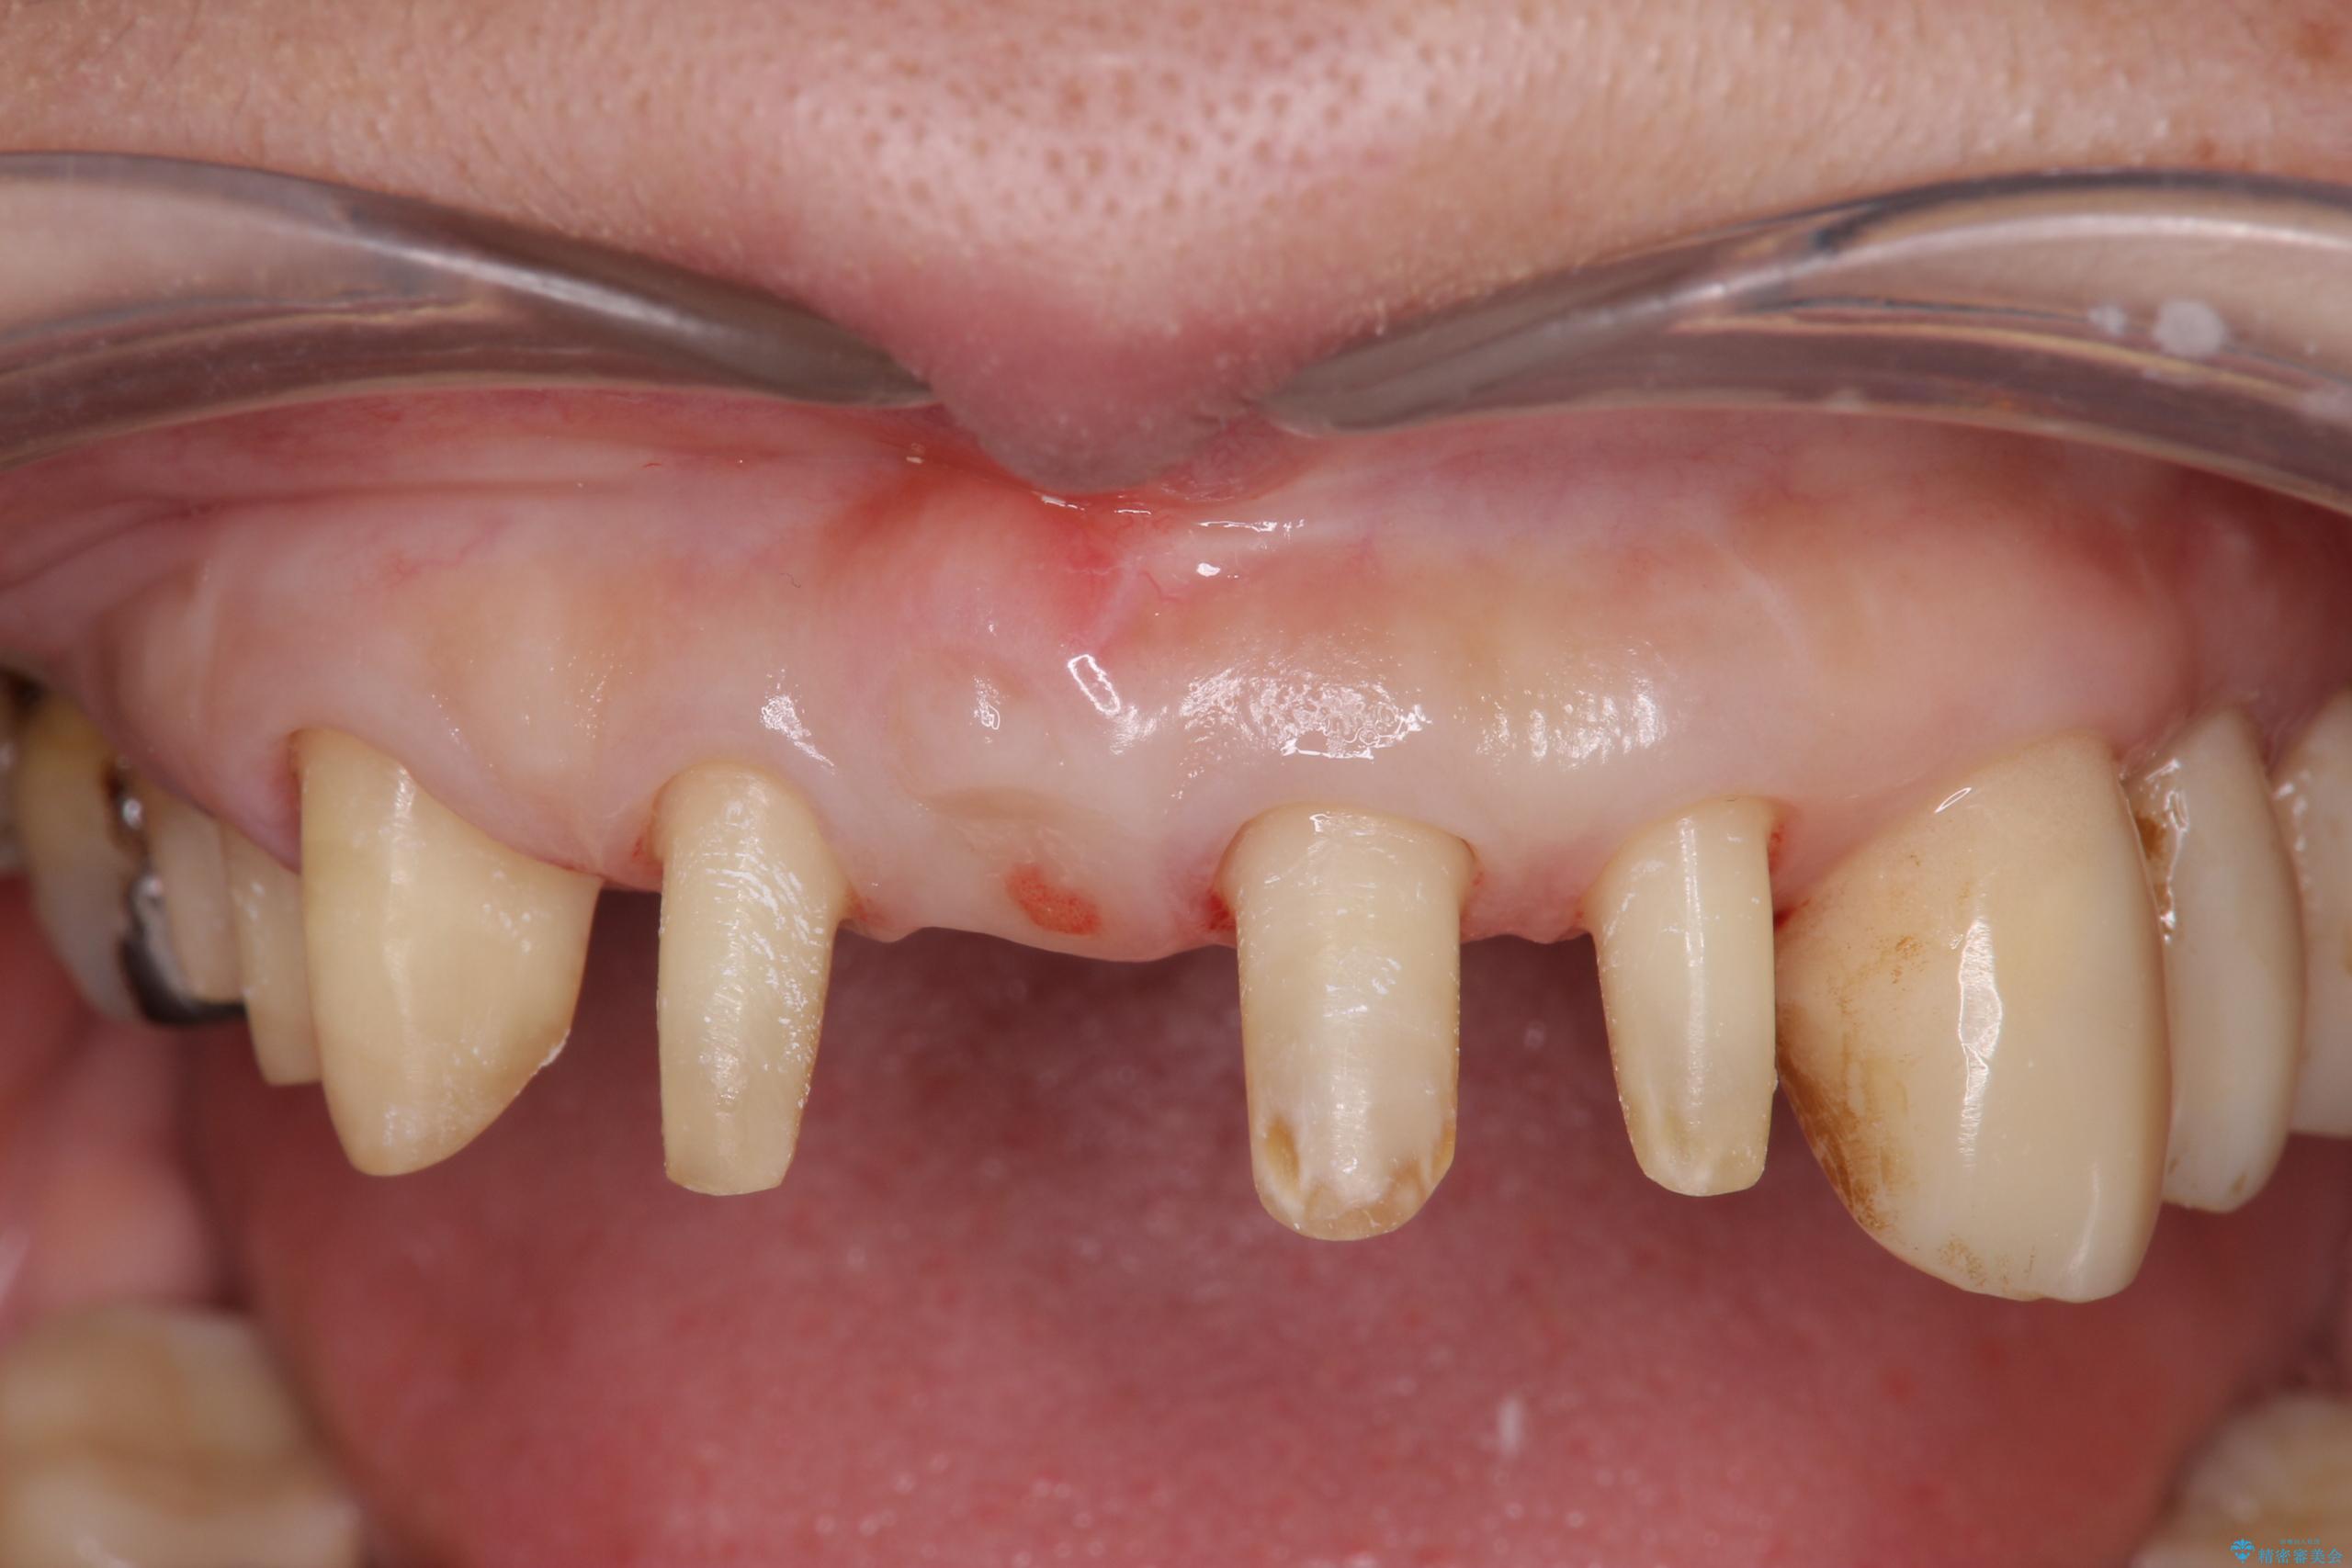

長年、他院にて定期管理および歯周病治療を継続されていたものの、突然多数の抜歯を宣告されたことで治療方針に疑問を抱かれ、当院へ歯周病治療のご相談に来院されました。

検査の結果、歯周ポケットの測定値は4-6mm程度の値が全顎にわたって認められ、中等度歯周病の状態です。

歯を今後残し、歯周病の状態を改善するため、歯槽骨の再生治療をおこなったのち、歯周ポケットの除去、セラミックブリッジの製作を行う治療計画を実行していきます。

歯周病によって失われた歯を支える骨(歯槽骨)に対し、再生療法を用いることで骨の再生・回復を実現しました。骨の高さが改善されたことで、歯の土台が強化され、将来にわたって歯をしっかりと支え続けられる口腔内環境を整えることができました。